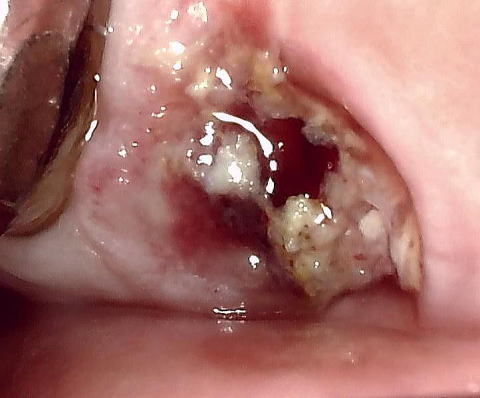

■ ドライソケット像

ドライソケット画像